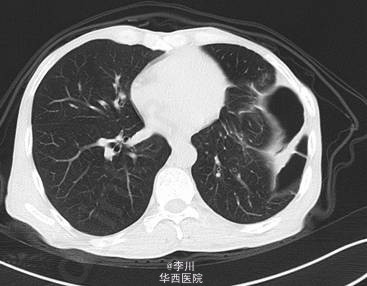

患者男,49岁9月,因“ 全腹胀痛14天,加重伴呕吐4天”入院。患者14天前在进食“甜酒”后出现腹部胀痛,逐渐扩大到整个腹部,伴恶心干呕,不伴寒战发热、腹泻、晕厥,无心悸、气促、发绀。外院诊断“肠梗阻”,予以石蜡油灌肠及输液治疗后缓解。4天前患者在进食后出现同前症状,遂于我院就诊。

既往患者1+年前因摔跤撞伤腹部,于贵阳医学院行“脾切除+膈疝修补术”。查体左肺呼吸音减弱,可问及异常肠鸣音。CT提示:左侧膈面上抬、局部膈肌软组织似不连续,可见胃及部分肠管上移,膈疝?

在全麻下经左胸膈疝修补、胸膜粘连烙断、胸腔闭式引流术。术中发现:左膈肌外侧缺损约15cm×12cm大小,腹腔内网膜、胃及横结肠等组织疝入胸腔。网膜、胃、结肠组织与膈肌、胸壁片状粘连。左侧肺与胸壁广泛粘连。术后予抗炎、化痰、对症等治疗后好转。